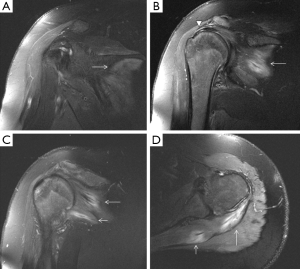

A normal pectoralis major tendon should have uniform low signal intensity on MR imaging. Like US (34), tears of the pectoralis major tendon seen on MR imaging exhibit different degrees of tendon abnormality, depending on the degree of injury. A grade I strain of the muscle belly will have feathery intramuscular fluid-sensitive signal intensity, which represents oedema and/or haemorrhage. Grade II injury will appear as a partial tear with an intramuscular hematoma, while grade III injury has a complete tear with possible retraction (Figures 11-13). As a matter of fact, a partial tear involving only the posterior sternal segments, the anterior clavicular head and tendon will be intact, with the long head of the biceps tendon in place. With complete tears involving both the sternal head and the clavicular head, however, there will be disruption of the entire tendon, with anterior displacement of the long head of the biceps tendon (35).

The rotator cuff stabilizes the humeral head in the glenoid cavity and comprises the supraspinatus, infraspinatus, teres minor and the subscapularis muscles and tendons. They all originate in the scapula (the supraspinatus on the supraspinous fossa, the infraspinatus on the infraspinous process, the teres minor on the posterior surface of the scapula and the subscapularis on the subscapular fossa), and their tendons insert on the humerus (the first three on the greater tubercle of the humerus, and the subscapularis on the lesser tubercle). Tears of the rotator cuff are more common in older patients, generally associated with degenerative changes (the supraspinatus being the most commonly involved). However, acute traumatic tears can also occur in young and athletic individuals. Lesions usually affect the humeral insertion of the rotator cuff tendons, but can also more rarely affect their muscular origins in the scapula. Clinical examination and plain radiographs are almost never helpful in predicting rotator cuff muscle tears immediately after trauma, whereas MRI has proven its usefulness in the assessment of these lesions (Figure 14). Patients with injuries at the muscle origin or belly are treated conservatively (38).